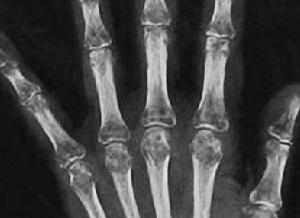

1.放射學檢查 X 線平片通常顯示節段性骨質缺乏,典型者可見四肢長骨和手足短骨斑片狀脫鈣和軟組織水腫。高分辨力X 線片還可顯示骨膜下吸收、條紋形成、骨膜下洞孔和隧道形成。受累四肢行CT 和MRI 檢查似乎價值不大或無診斷意義。